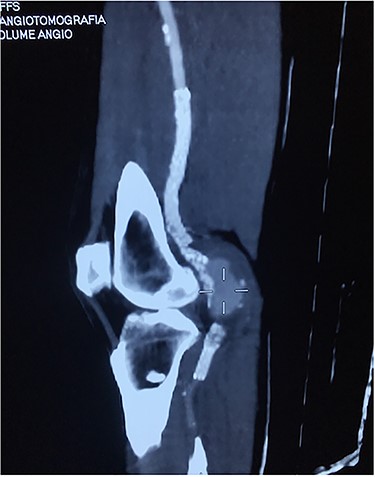

Approval for retrospective reports is not required by our institutional review board. This study is in accordance with the principles of the Declaration of Helsinki. A 77-year-old man with multiple comorbidities, including coronary vascular disease, hypertension, dyslipidemia, previous right carotid endarterectomy, and endovascular aortic repair (in 2011), was referred to our unit for evaluation of a retropopliteal pulsatile mass. He had undergone infra-popliteal stenting 18 months earlier, to treat peripheral arterial disease with severe left claudication. The procedure was performed at another vascular institute, and the stent type was unknown. Physical examination revealed the presence of a femoral and popliteal pulse and the absence of tibial pulses; at admission, the ankle–brachial index was 0.8. According to the patient, he had noticed the mass in the last 2 months prior to admission, but the absence of pain delayed his presentation to the hospital. An ultrasound scan was performed on admission and revealed a large popliteal pseudoaneurysm with normal flow present distally, and fracture of the stent was confirmed by computed tomography, which also detected a 4.2 cm dilatation of the left popliteal artery (Figs 1–3).

Angiotomography revealed fracture of a stent deployed in the popliteal artery and a pseudoaneurysm formation of size 4.2 cm at the part of stent fracture.

Angiotomography of the popliteal region highlighted the complete stent fracture and a large pseudoaneurysm formation.

Angiotomography showing a fractured stent and pseudoaneurysm at the site of the fracture.